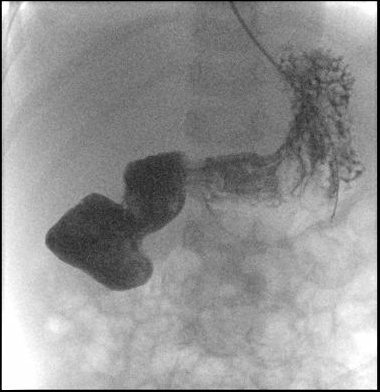

He had an extensive evaluation. After he had stabilized and then markedly improved (12 days after admission), an UGI study demonstrated an obstruction near the 2nd-3rd portion of the duodenum with a dilated proximal duodenum.

UGI study: